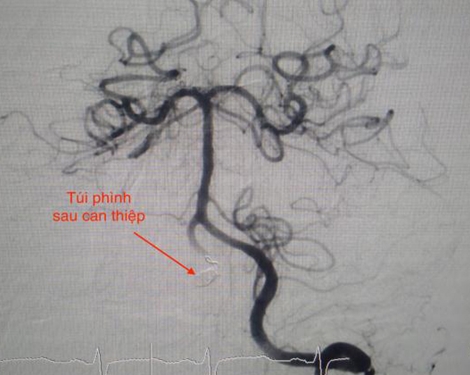

Ngày 15-7, TS-BS Trần Chí Cường, Giám đốc Bệnh viện đột quỵ tim mạch (BVĐQTM) Cần Thơ cho biết, các BS của BV vừa cứu sống bà Đ.T.Đ (73 tuổi, ngụ quận Cái Răng, TP Cần Thơ), bị tràng dịch màng ngoài tim, ngưng tim, ngưng thở.